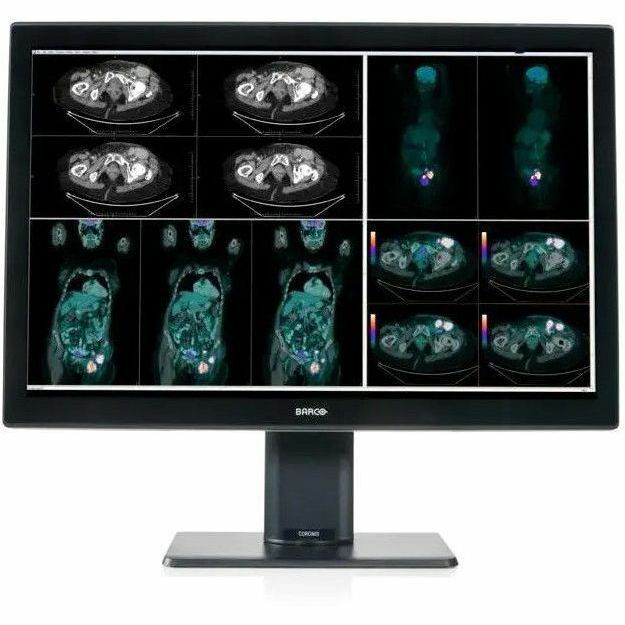

Barco Coronis Fusion MDCCâ€'4430 30" Class WQXGA LED Monitor - 16:10 - Black, White

| Product Name | Coronis Fusion MDCC-4430 Widescreen LED Monitor |

| Marketing Information | A brighter diagnosis Coronis Fusion, Barco's renowned multi-modality display for radiologists, now comes in a new, energy-efficient and lightweight design. Bright on so many levels, Coronis Fusion has been designed to help radiologists provide care with confidence. See more details quickly thanks to the high brightness, high contrast ratio and best-in-class image quality. What's more, the wide color gamut in combination with SteadyColor™ calibration technology helps you see even more colors and more details on the 30-inch screen. Smart workflow Designed for your comfort and to boost productivity, Coronis Fusion comes with smart image-enhancing features and workflow tools. The display's wide viewing angle combined with the SoftGlow™ task and wall light help reduce eye strain. Thanks to SpotView, radiologists can further improve detection accuracy as well as reading productivity. Effortless quality & compliance Like all of Barco's medical display systems, Coronis Fusion comes with QAWeb Enterprise, a cloud-based technology for automated calibration, Quality Assurance and compliance to ensure maximum uptime of the display with no need for human intervention. A one-stop-shop solution Barco medical display systems include exclusive display controllers that are validated with the latest workstations and with all major PACS applications. All components are under the full 5-year warranty (including the display backlight) for complete peace of mind. Ensuring diagnostic confidence with MDR Class IIa Our radiology displays are MDR-certified as Class IIa. Their product information has been reviewed and cleared by independent medical and technical experts, and is audited yearly. In other words, we ensure diagnostic confidence and peace of mind for our users. |